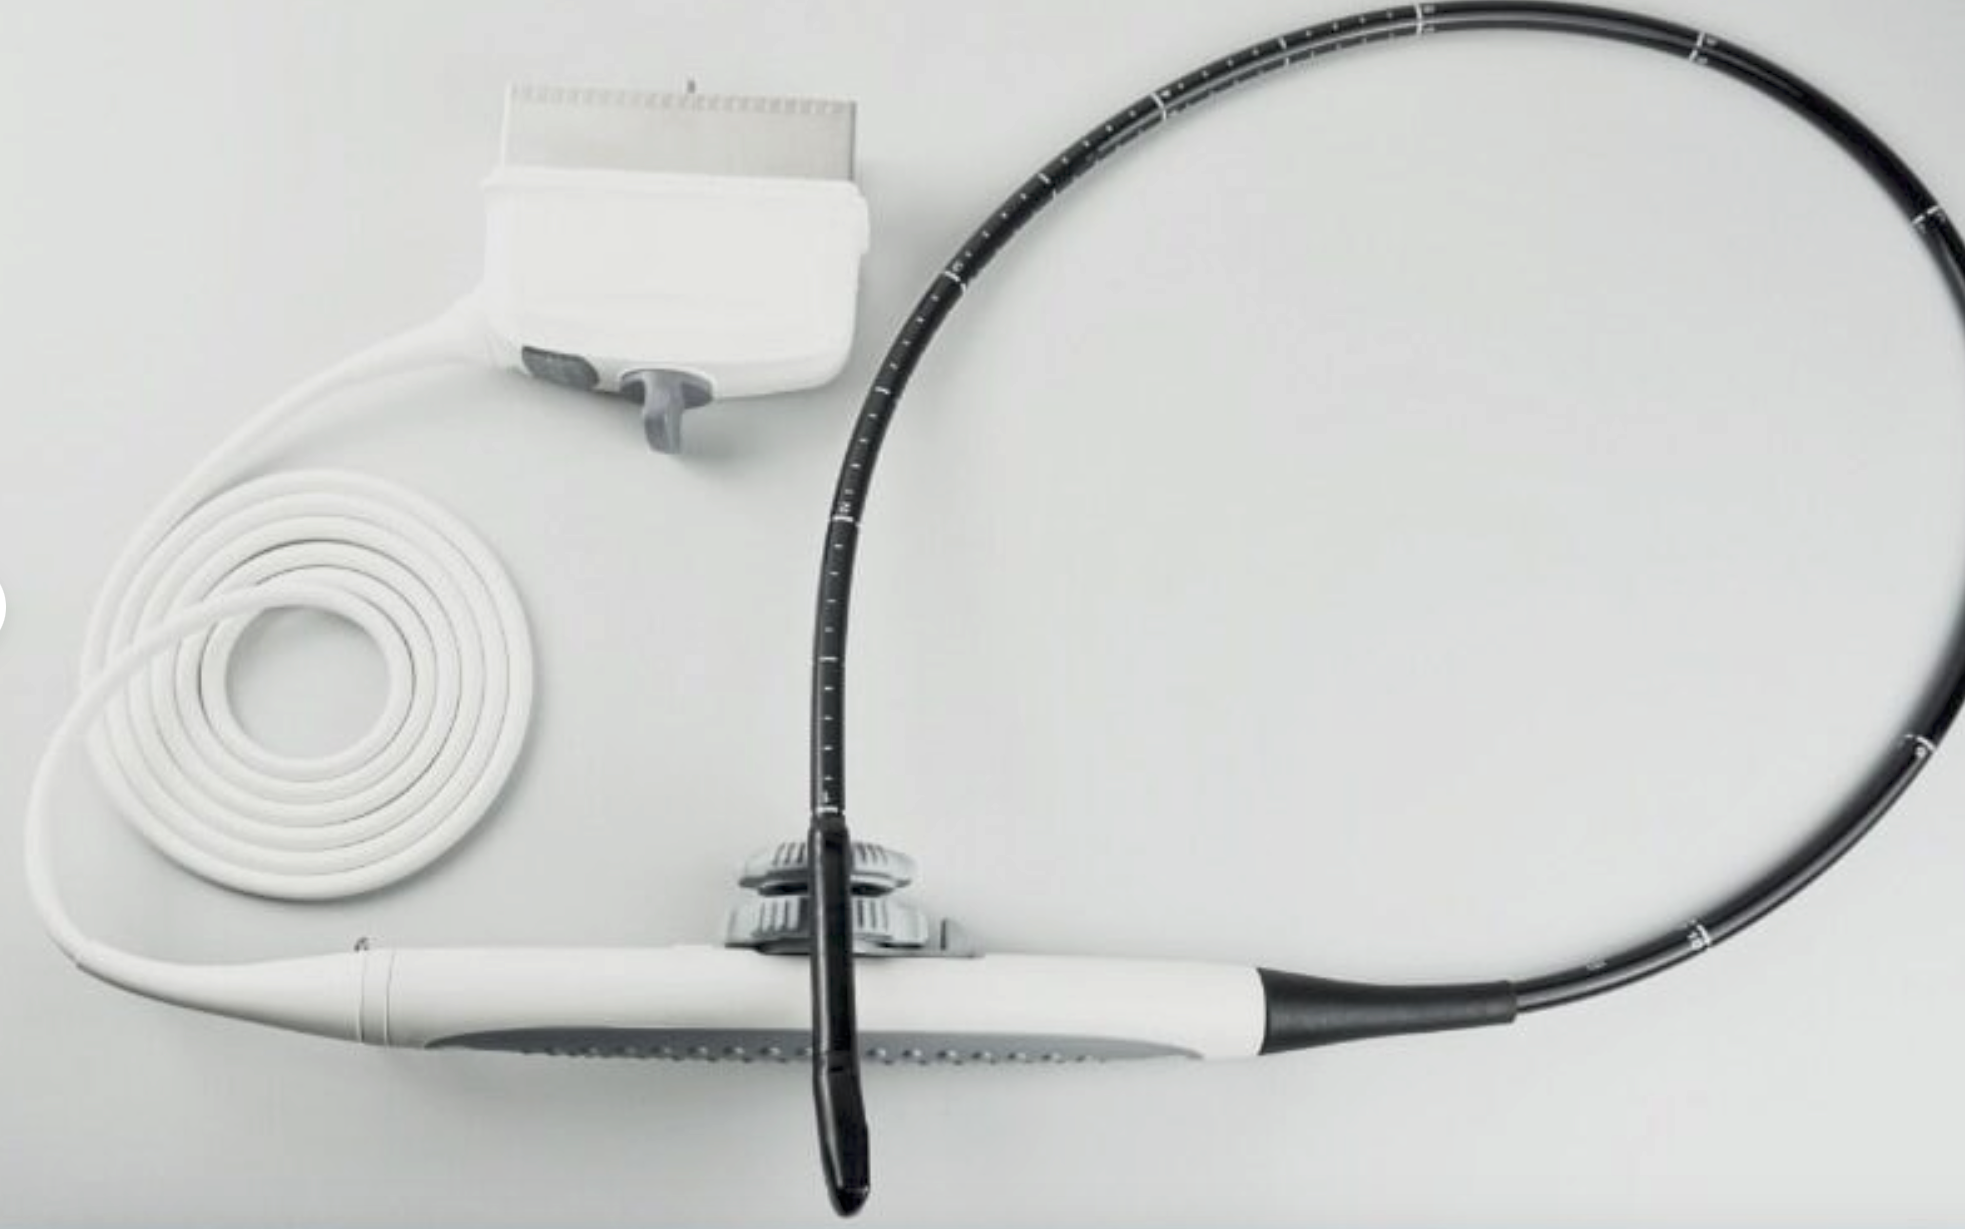

Save $ 179.82

DIAGNOSTIC ULTRASOUND MACHINES FOR SALE

Philips S7-2 Ultrasound TEE Probe (54DM)

Sale price$ 819.18

Regular price$ 999.00